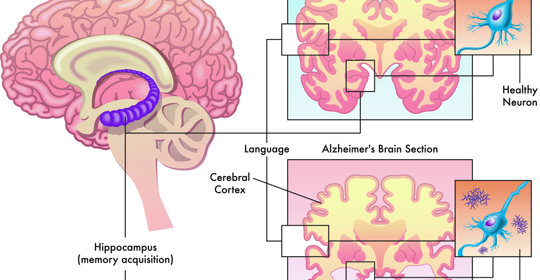

糧食短缺與腦波異常:氣候變化與腦波異常的治療